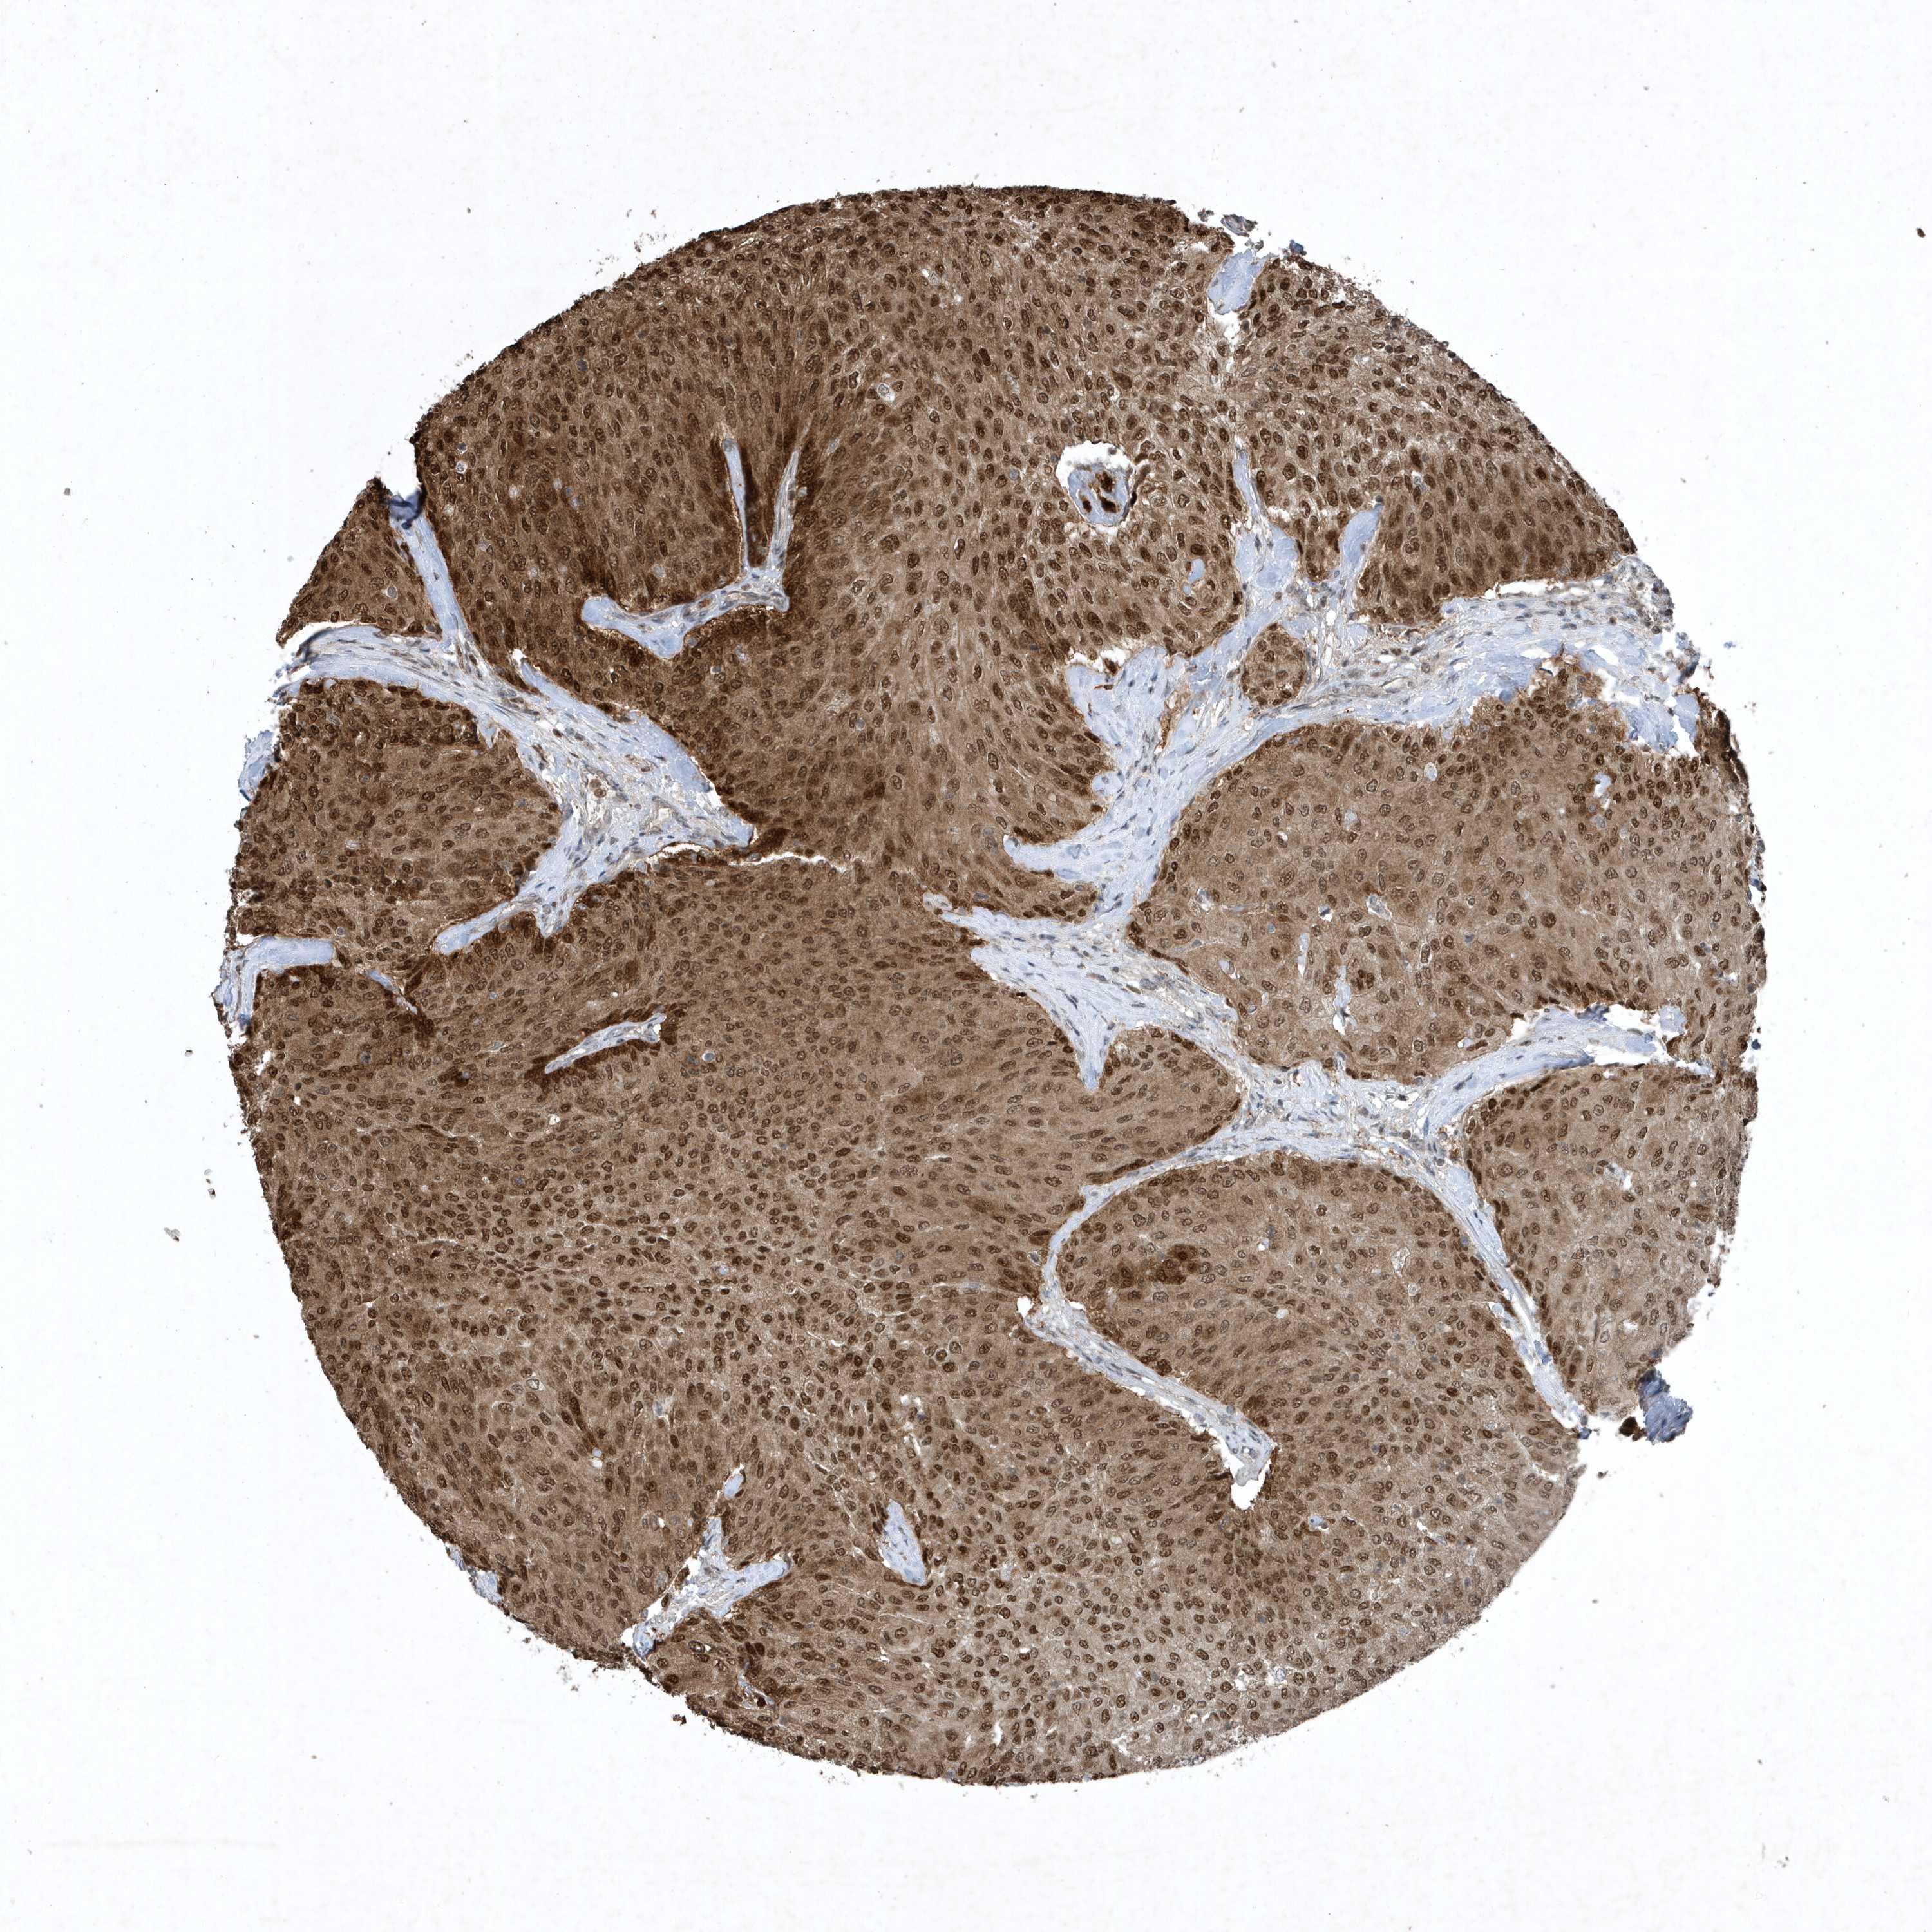

UROTHELIAL CANCER - Protein expressioni

A mouse-over function shows sample information and annotation data. Click on an image to view it in a full screen mode. Samples can be filtered based on level of antibody staining by selecting one or several of the following categories: high, medium, low and not detected. The assay and annotation is described here.

Note that samples used for immunohistochemistry by the Human Protein Atlas do not correspond to samples in the TCGA dataset.

Antibody stainingi

Antibody staining in the annotated cell types in the current human tissue is reported as not detected, low, medium, or high, based on conventional immunohistochemistry profiling in selected tissues. This score is based on the combination of the staining intensity and fraction of stained cells.

Each image is clickable and will lead to virtual microscopy that enables deeper exploration of all samples and also displays staining intensity scores, fraction scores and subcellular localization as well as patient and tissue information for each sample.

Antibody HPA052504

Antibody CAB017451

Antibody CAB032815

Staining

High

Medium

Low

Not detected

Intensity

Strong

Moderate

Weak

Negative

Quantity

>75%

75%-25%

<25%

None

Location

Nuclear

Cytoplasmic/membranous

Cytoplasmic/membranous,nuclear

Urothelial carcinoma, High grade

Urothelial carcinoma, NOS

Urothelial carcinoma, Low grade